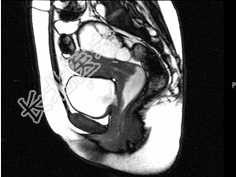

- 多项选择题女,28岁, 阴道有异常液体流下,CT和MRI扫描如图, 以下诊断正确的是( )

A、MRI的T2加权像示宫颈阴道内有大片状高信号影

B、CT增强示造影剂由膀胱进入阴道

C、膀胱后下缘可见鸟嘴状突起

D、考虑为膀胱阴道瘘

E、考虑为左侧输尿管异位开口